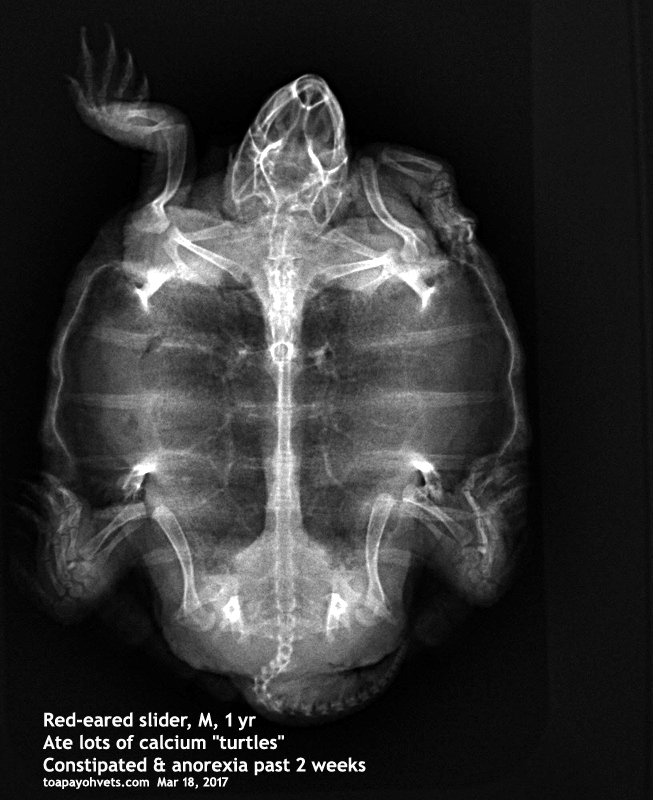

Male, RES, 1 yr

Losing appetite 4 weeks ago and 2 weeks ago, anorexic.

"He would chew at the "calcium" turtles as if they were real ones," the young man was much

worried about his RES losing weight and having no appetite. "He just ate and ate."

"How many 'calcium turtles' did he chewed and swallowed?" I asked.

"Many, many," he replied.

X-rays are taken today.

There could be calcium impaction at the vent area although it is hard to say.